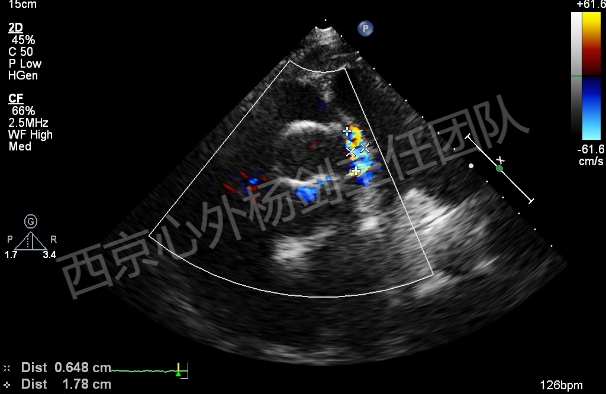

患者李某某,男,61岁,现病史:高血压15年,15年前行主动脉瓣置换术,13年前行升主动脉置换术、冠状动脉旁路移植术。主因心脏瓣膜术后15年,突发胸闷气短20天入院。检查提示:主动脉夹层动脉瘤,主动脉瓣位机械瓣位置、动度未见异常,升主动脉位人工血管上段吻合口漏,原有升主动脉管壁与人工血管之间液区,向右房分流,肺动脉高压(收缩压约51mmHg)。EDV: 192ml, ESV:102ml, FS:23%, SV:89ml。

术中操作